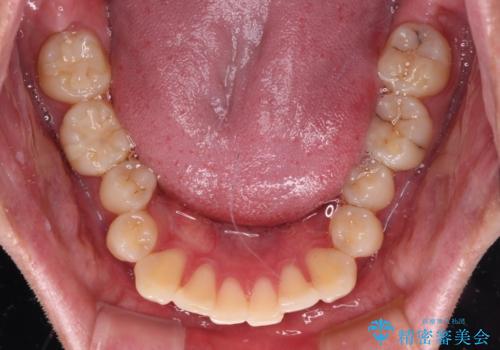

上下のデコボコを治したい インビザラインによる矯正治療

- 前歯のデコボコと突出感を気にして来院された患者様です。

極力目立たない装置を希望とのことで、インビザラインを用いて非抜歯で矯正治療を行うこととしました。

事前に親知らず4本を抜歯し、多少歯列を後方に移動できるように準備をした上で、なるべく歯と歯の間を削ることなくデコボコを解消できるように計画しました。